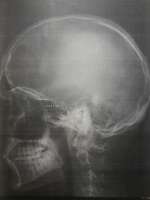

>>493043

Вот мрт. Я не хотел здесь никому навязываться, так что отвечай по желанию.

Кажется, к снимкам сопровождались комментарии, но я их не помню и видел вскользь. Возможно только они и нужны, а не снимки

>>493069

мда, загуглил и похоже это не мрт

>>493071

Совершенно верно. Это рентгеновские снимки и информацию они дают (почти) только о состоянии костей.